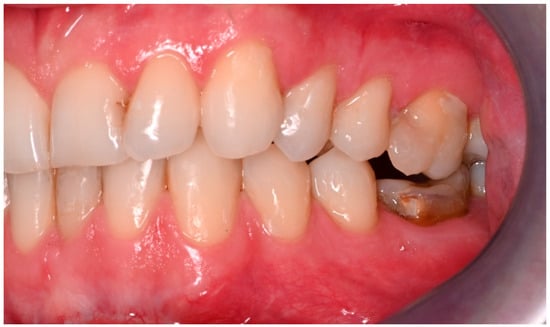

Figure 6. Inadequate occlusion with crossbite on the right-hand side after insufficient reduction in the condylar neck on the same side (see Figure 5).

Figure 7. Adequate occlusion on the left-hand side, after satisfactory reduction in the condylar neck on the same side. The lower molar crown was fractured in the accident (see Figure 5).

Two operations had to be redone because of inadequate reposition in the symphysis/parasymphysis with broad (>2 mm) lingual splay. In both cases, straight miniplates were removed. Osteosynthesis was achieved with lag screws. Figure 3 depicts plate osteosynthesis of a symphyseal fracture with a broad lingual gap (Figure 3). Figure 4 shows the same patient after redo operation and osteosynthesis of the same fracture with a lag-screw and a marked reduction in the lingual splaying (Figure 4). Figure 5 demonstrates the condylar reduction in the frontal plane in the same patient. Figure 6 and Figure 7 show the patient’s occlusion (Figure 5, Figure 6 and Figure 7). The third redo operation was due to nonunion and infection of an angular fracture with fracture of the two condylar plates. In this case, after removal of the infected miniplate, the angle fracture was stabilized with a reconstruction plate and a miniplate from an extraoral approach; the two broken miniplates at the condylar process were left in situ.